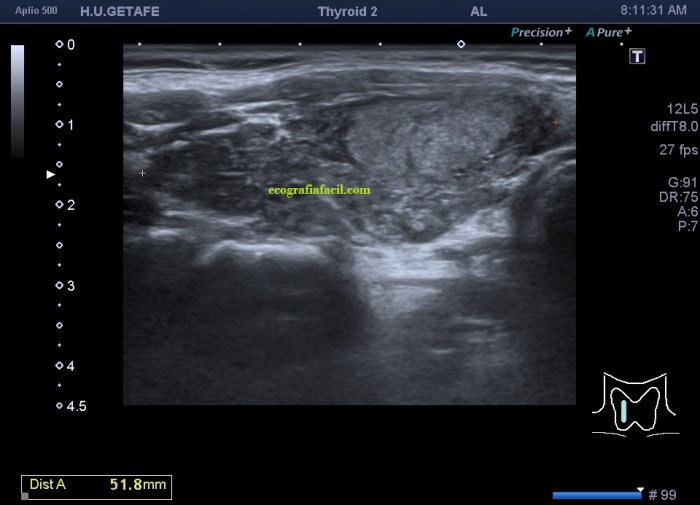

Era un nódulo hiperecogénico en el contexto de la tiroiditis en el estudio de una ecografía tiroidea.

Te enseño las imágenes, típicas de una exploración tiroidea de protocolo con semiología de tiroiditis.

Mira las imágenes y luego te explico un poco, poco, porque no tiene mucho que explicar…

De la imagen 1 a 7 el protocolo habitual, el estudio particular del nódulo con medidas y aplicación del doppler demuestra el aspecto típico del Caballero Blanco.

Resumen de las imágenes que has visto en el caso de hoy:

- Hipoecogenicidad del parénquima

- Heteroecogenicidad

- Múltiples nódulos hipoecoicos muy pequeños

El Caballero blanco, recibe el nombre debido a su semiología hiperecogénica, homogénea y solitaria circunscrito en la patología referida con anterioridad, puede aparecer en esta patología de forma benigna o degenerar en otro tipo de patología a formas malignas como el linfoma tiroideo.